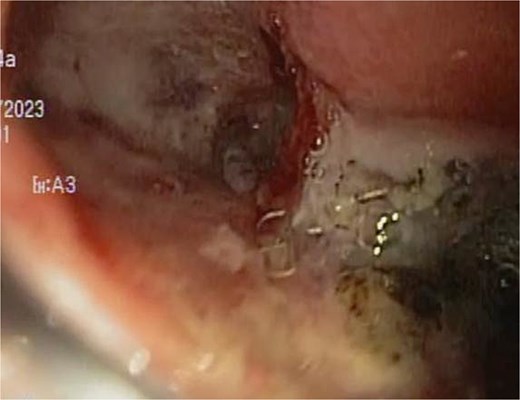

A 48-year-old female without comorbidities underwent vertical sleeve gastrectomy for grade II obesity, developing a leak in the upper third of the sleeve, presenting with a productive cough. Endoscopy revealed a 15 mm fistula (Fig. 6). EVAC therapy was initiated with changes every 3–5 days (Fig. 7). The patient showed slow evolution, developing an intragastric abscess and productive cough. After nine changes over 45 days, endoscopy showed complete resolution of the fistula (Fig. 8).

Upon removing the EVAC sponge, we can observe a clean cavernous cavity with minimal fibrin and granulation tissue.